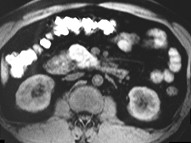

男,43岁,上腹胀痛2个月,频繁呕吐,呕吐物为黄绿色,影像所见如图,可能的诊断为()

男,43岁,上腹胀痛2个月,频繁呕吐,呕吐物为黄绿色,影像所见如图,可能的诊断为

[单选题]男,43岁,上腹胀痛2个月,频繁呕吐,呕吐物为黄绿色,影像所见如图,可能的诊断为()A .十二指肠溃疡B .十二指肠结核C .十二指肠中分化腺癌D .十二指肠克罗恩病E .十二指肠淋巴瘤